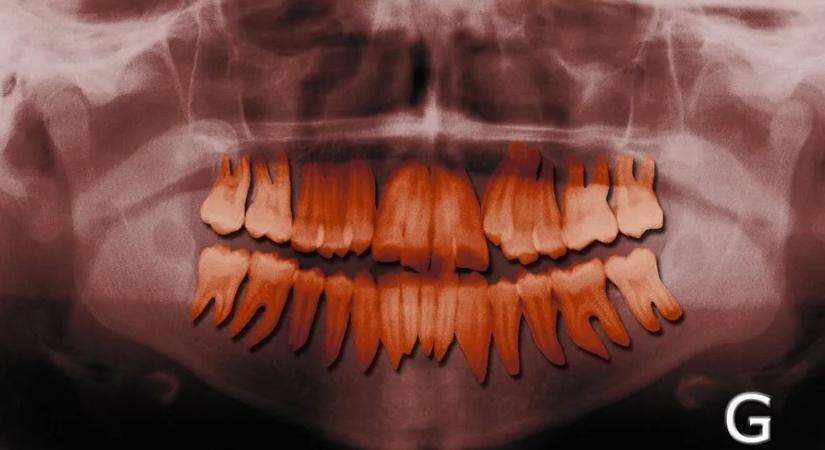

Itt a meglepő válasz: miért nem számítanak a fogak csontnak 2026.01.05. 14:50 Kárpátinfo fogak csont Csak látszólagos a hasonlóság. Elolvasom a cikket >> - Hirdetés -

A Fogtündért is elérte az infláció, két év esés után durván drágulnak a tejfogak Ma 15:24 VG Infláció fogak